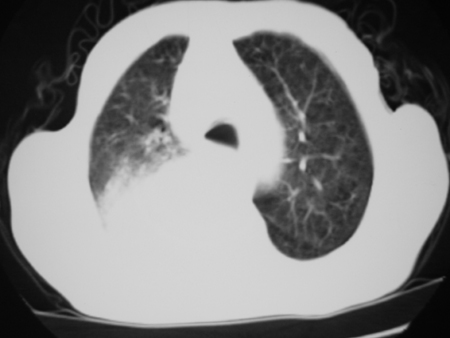

标题: CT24778:肺部病变

男77岁,胸痛就诊

右侧胸腔积液,部分包裹,右下肺膨胀不全,右下肺感染。

考虑右肺门占位并下叶不张 右胸包裹积液

右肺中叶及下叶炎症并胸腔积液(部分包裹),建议抽液后复查ct除外占位。